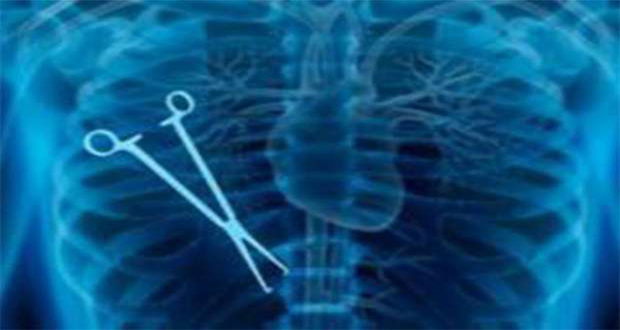

تفاجأ أطباء بوجود مقص جراحة في بطن سيدة جزائرية عانت على مدى سنوات من آلام حادة في المعدة بعد أن خضعت لعملية قيصرية لولادة طفلها في إحدى مستشفيات العاصمة.

وذكرت وسائل اعلام جزائرية أن الأطباء حاولوا لعدة سنوات مضت معالجة السيدة عبر مدها بأدوية علاج المعدة والقولون وبعد أن زاد الألم بمرور الوقت قررت المرأة مؤخرا إجراء فحص الماسح الضوئي سكانير ليفاجأ الطبيب بوجود قطعة معدنية في بطنها وتبين لاحقا أن الأمر يتعلق بمقص جراحة كان الأطباء قد نسوه في بطنها.

فما كان من المريضة إلا العودة مجدداً للمستشفى نفسه وواجهتهم بالأمر وبعد شدّ وجذب قرروا إجراء عملية أخرى وبالفعل تم استخراج المقص.